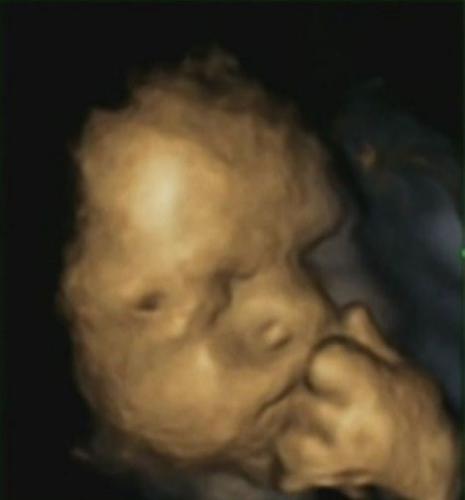

Фотографски доказ бебињата во стомакот го чувствуваат стресот на мајката?

Со помош на 4Д ултразвук истражувачите направиле восхитувачки јасни 3Д слики на бебиња во стомакот на мајката. Се покажало дека бебињата на мајките под стрес, многу почесто ги допирале своите лица.

Слика од лицето на бебе во стомакот на мајката е нешто толку прекрасно, но студијата покажала дека кога мајките биле под стрес, се чувстувале беспомошно или под притисок, бебињата почесто со рацете ги допирале своите лица.

Сликите се направени така што со посебна 4Д машина се направени слики од различни агли за да се створи една јасна, тридимензионална слика, а потоа se снимени како видео за да се добие четврта димензија.